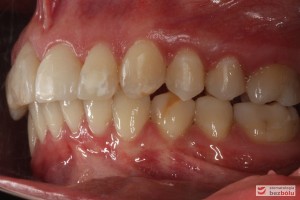

Pacjentka lat 26 zgłosiła się do gabinetu celem korekcji uśmiechu. Głównym zmartwieniem były problemy estetyczne, które znacznie wpływały na jakość życia pacjentki. Wykonano leczenie zachowawcze zębów oraz analizę cefalometryczną i analizę modeli diagnostycznych. Zaplanowano leczenie aktywne aparatem DAMON dla szczęki i żuchwy, które trwało 2 lata. Po fazie leczenia aktywnego rozpoczęto leczenie retencyjne z użyciem szyny tłoczonej dla szczęki i retainera stałego dla żuchwy.